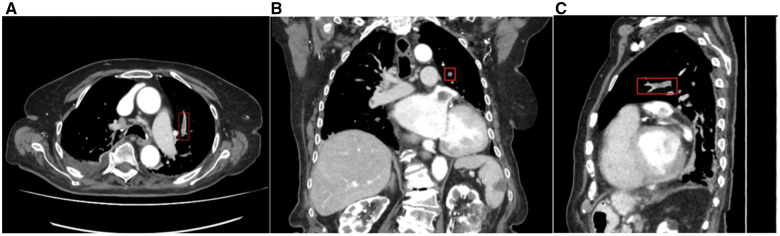

Materials and methods: A commercially available deep learning-based software, CINA-iPE (Avicenna.AI, La Ciotat, France), analyzes CECT images to highlight suspected incidental PE cases. Consecutive retrospective CECTs from 5 clinical centers, not performed for PE evaluation, were collected until a selected balanced dataset between positive and negative cases was obtained. The reference standard was established by three independent U.S. board-certified radiologists reviewing the same images. Diagnostic performance and the time-to-notification (from data acquisition to processing of results) were computed.

Results: A total of 381 anonymized CECT cases were acquired on 39 different scanner models from GE, Philips, Siemens, and Canon. The algorithm correctly identified 159/181 exams positive for PE (sensitivity 87.8% [95% CI: 82.2%-92.2%]) and 184/200 exams negative for PE (specificity 92.0% [95% CI: 87.3%-95.4%]), yielding an accuracy of 90.0% [95% CI: 86.6%-92.8%]. Of 16 detected false positive cases, 50% were complex CECTs subject to disagreement among the reference read radiologists. The device missed 22 pulmonary embolisms, with 45.5% of them being complex cases and subject to disagreement among reviewers. The time from data acquisition to processing results was 1.5 ± 0.5 (mean ± SD, 95% CI: 1.4%-1.5%) minutes.